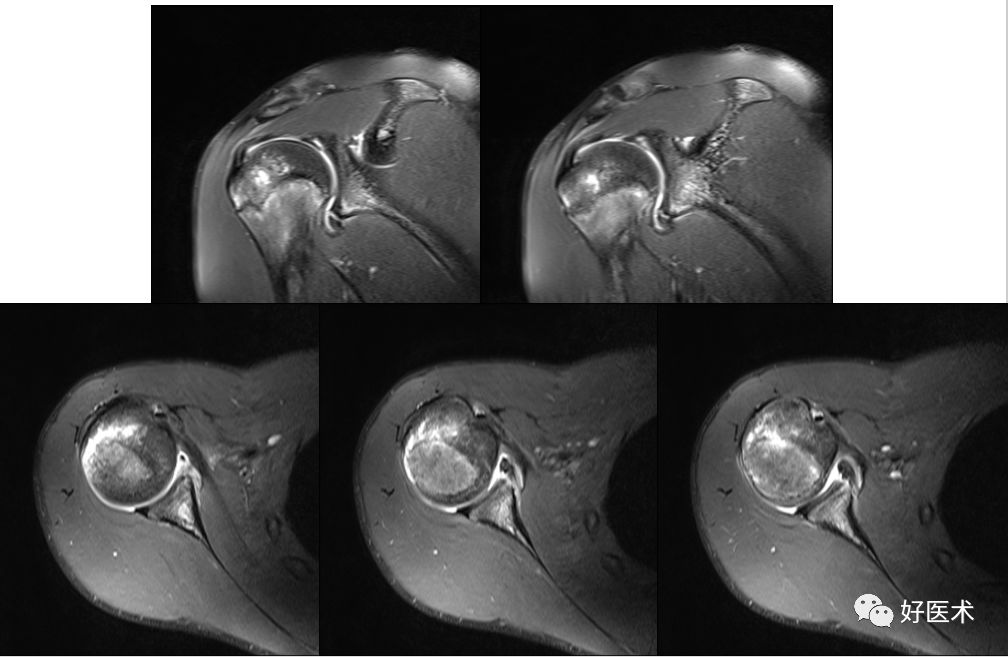

冈上下肌撕裂